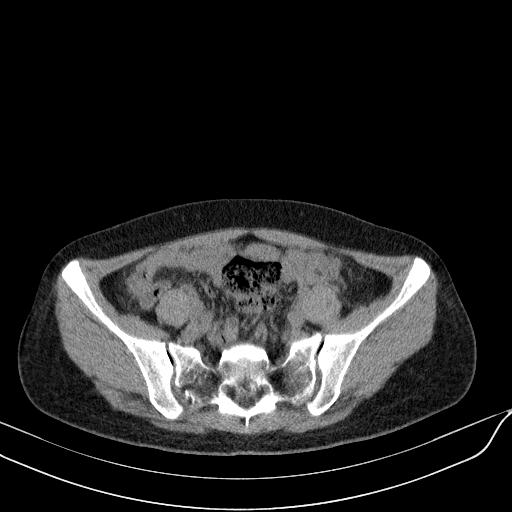

标题: CT23965:无外伤史,下腹痛 [打印本页]

标题: CT23965:无外伤史,下腹痛

肠道未准备,继续往下扫,乙状结肠占位不排除。建议钡灌或结肠镜检查。

乙状结肠占位不排除

未见明显异常改变,做个气钡双重造影除外一下结肠病变,无外伤史为啥不常规喝泛影葡胺水对比剂再扫ct呢?

扫描时应做肠道准备,口服稀释造影剂。

回肠间质瘤?

肠道肿瘤,建议行钡剂灌肠检查。